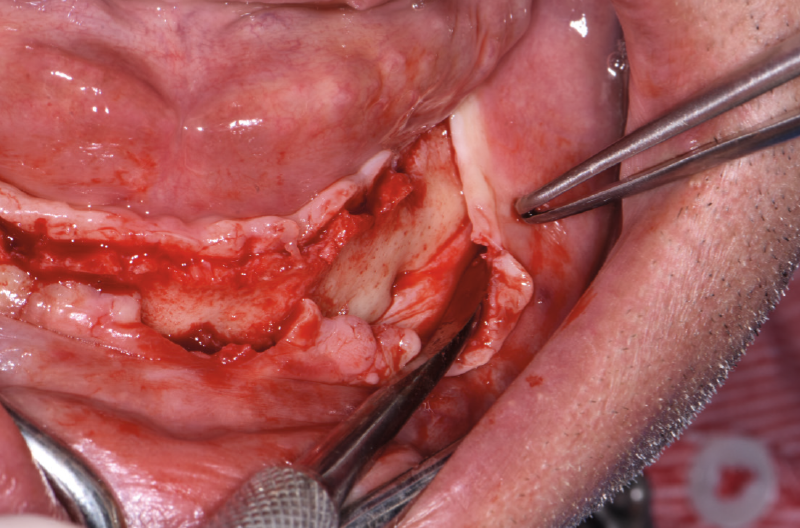

Exposición del orificio mentoniano izquierdo

Exposición del orificio mentoniano derecho